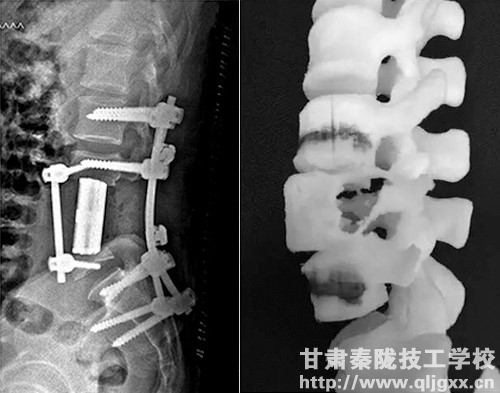

脊椎少一段,南医三院用3D打印脊骨接上了

近日,南方医科大学第三附属医院成功为一名脊索瘤患者切除脊椎上肿瘤,缺损的脊柱用3D打印的人工椎体置换。

3D假体设计3D打印换脊骨图片

3DACT人工椎体系统弥补了传统钛网类产品的应用不足,在骨与植入物的融合、避免椎体终板塌陷、组织结构重建等方面具有显著优势,更加符合人体力学和生理结构,术后骨愈合能力佳,发生并发症的几率大大降低。